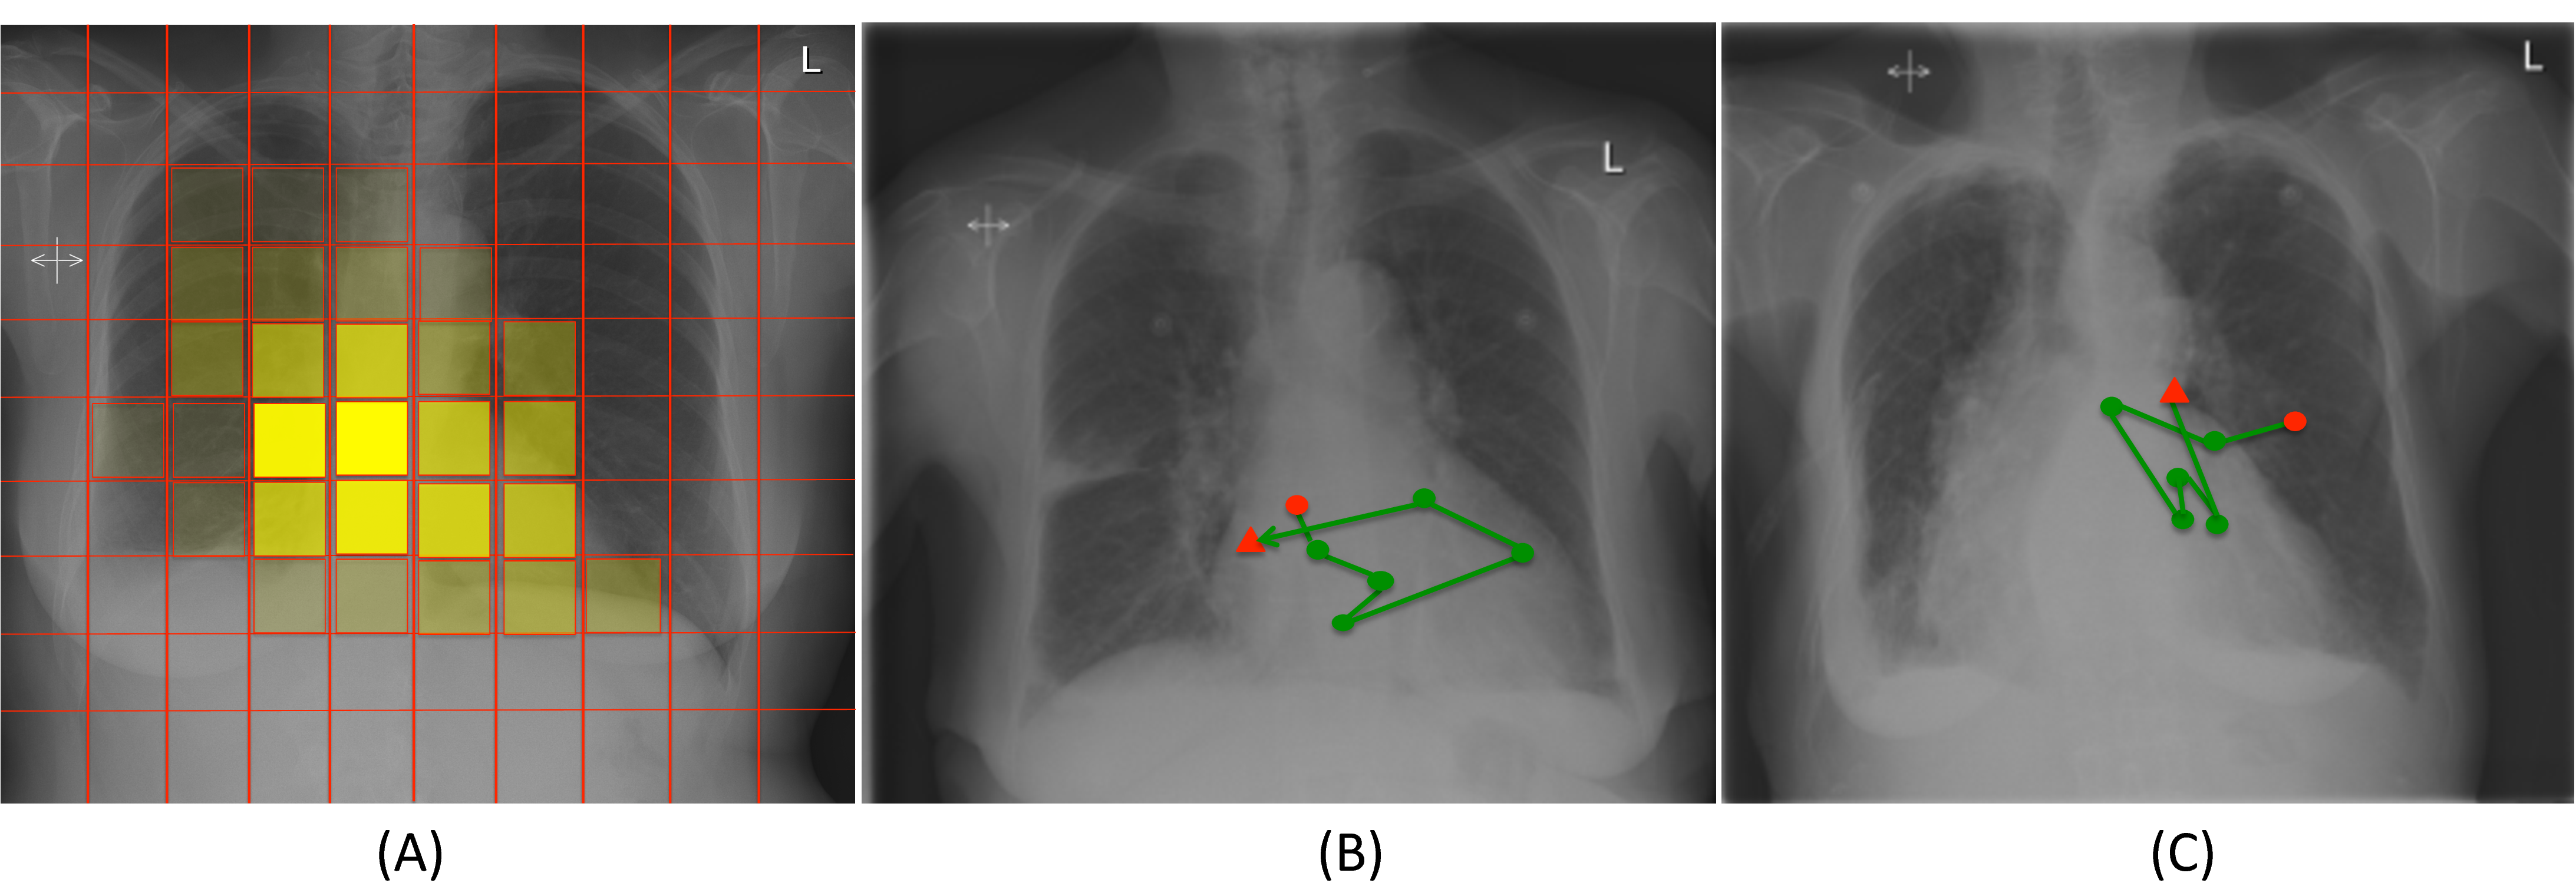

Figure 3 (A) shows the locations mostly attended by the RAM model when looking for medical devices. From this figure it is obvious that the learnt policy explores only the relevant areas where these devices can generally be found. Two examples of paths followed by the algorithm after learning the policy are illustrated in Figures 3 (B), (C). In these examples, starting from the center of the image, the algorithms moves closer to a region that is likely to contain a pacemaker, which is then correctly identified. The circle and triangle points (in red) indicate the coordinates of the first and last glimpse in the learnt policy, respectively.

Figure 3: (A) Image locations attended by the RAM model for the detection of medical devices. (B) and (C) are two different samples of the learnt policy on test images.